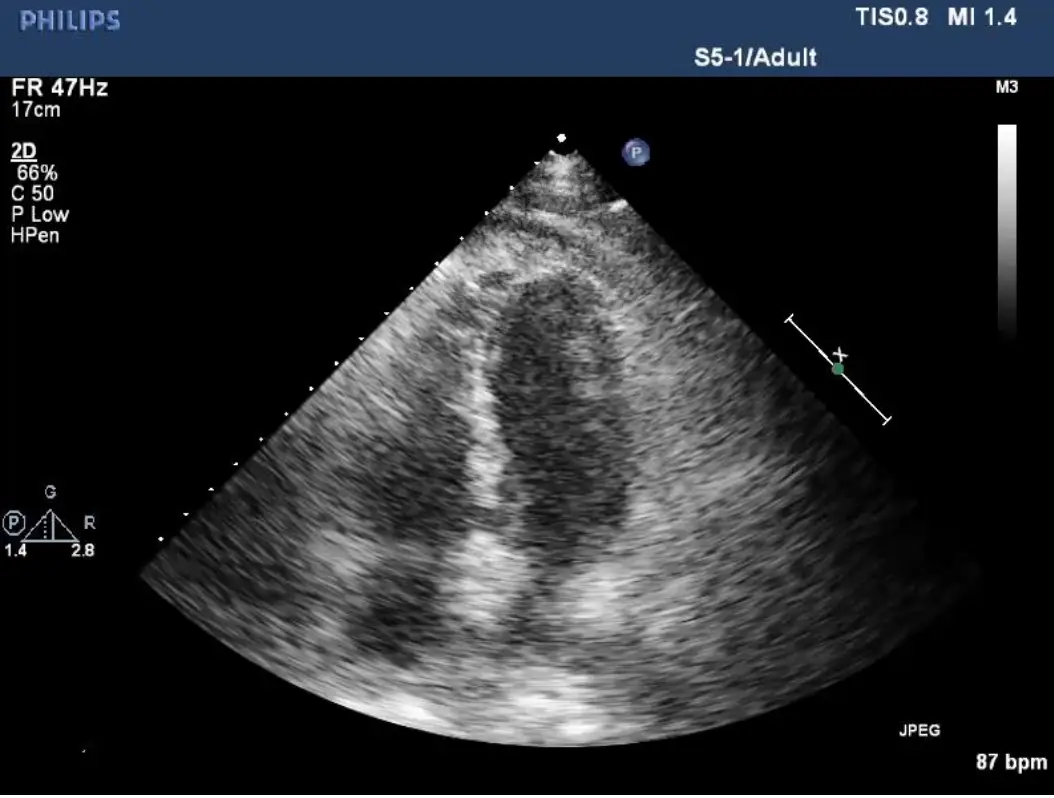

- 心臟超音波(Apical 4-chamber):雙側心房明顯擴大,心室腔徑偏小,心室壁厚而呈顆粒狀 “sparkling” 外觀,收縮功能近正常但舒張室腔幾乎不張—符合 infiltrative RCM。